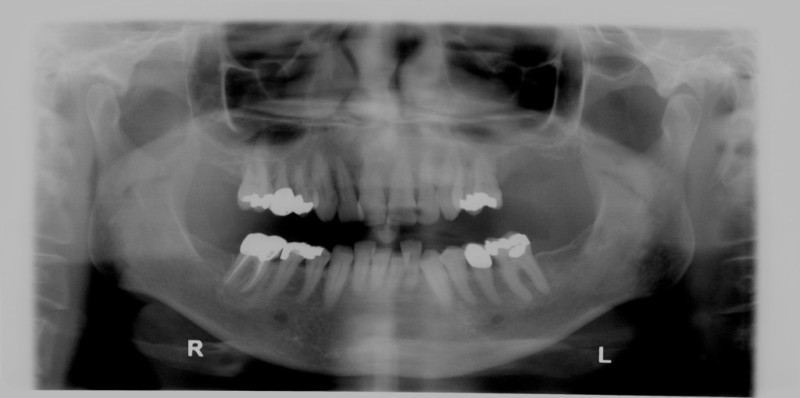

Alveolar Cleft (Defect in the Upper Jaw) Repaired with a Hip Bone Graft

Before